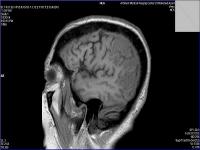

Medical imaging is an important investigative tool will help doctors to reach for the diagnosis of certain diseases, and the the advanced and high-quality imaging technologies are an important factor in maintaining the health of patients and accurate diagnosis of pathological lesions.